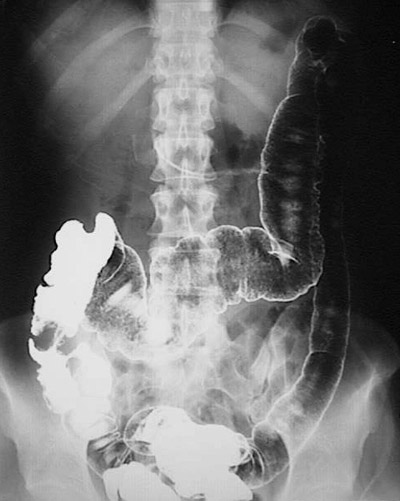

This barium enema demonstrates coarse granularity of the mucosa from the rectum to the transverse colon, typical of a more severe involvement of the mucosa with ulcerative colitis.